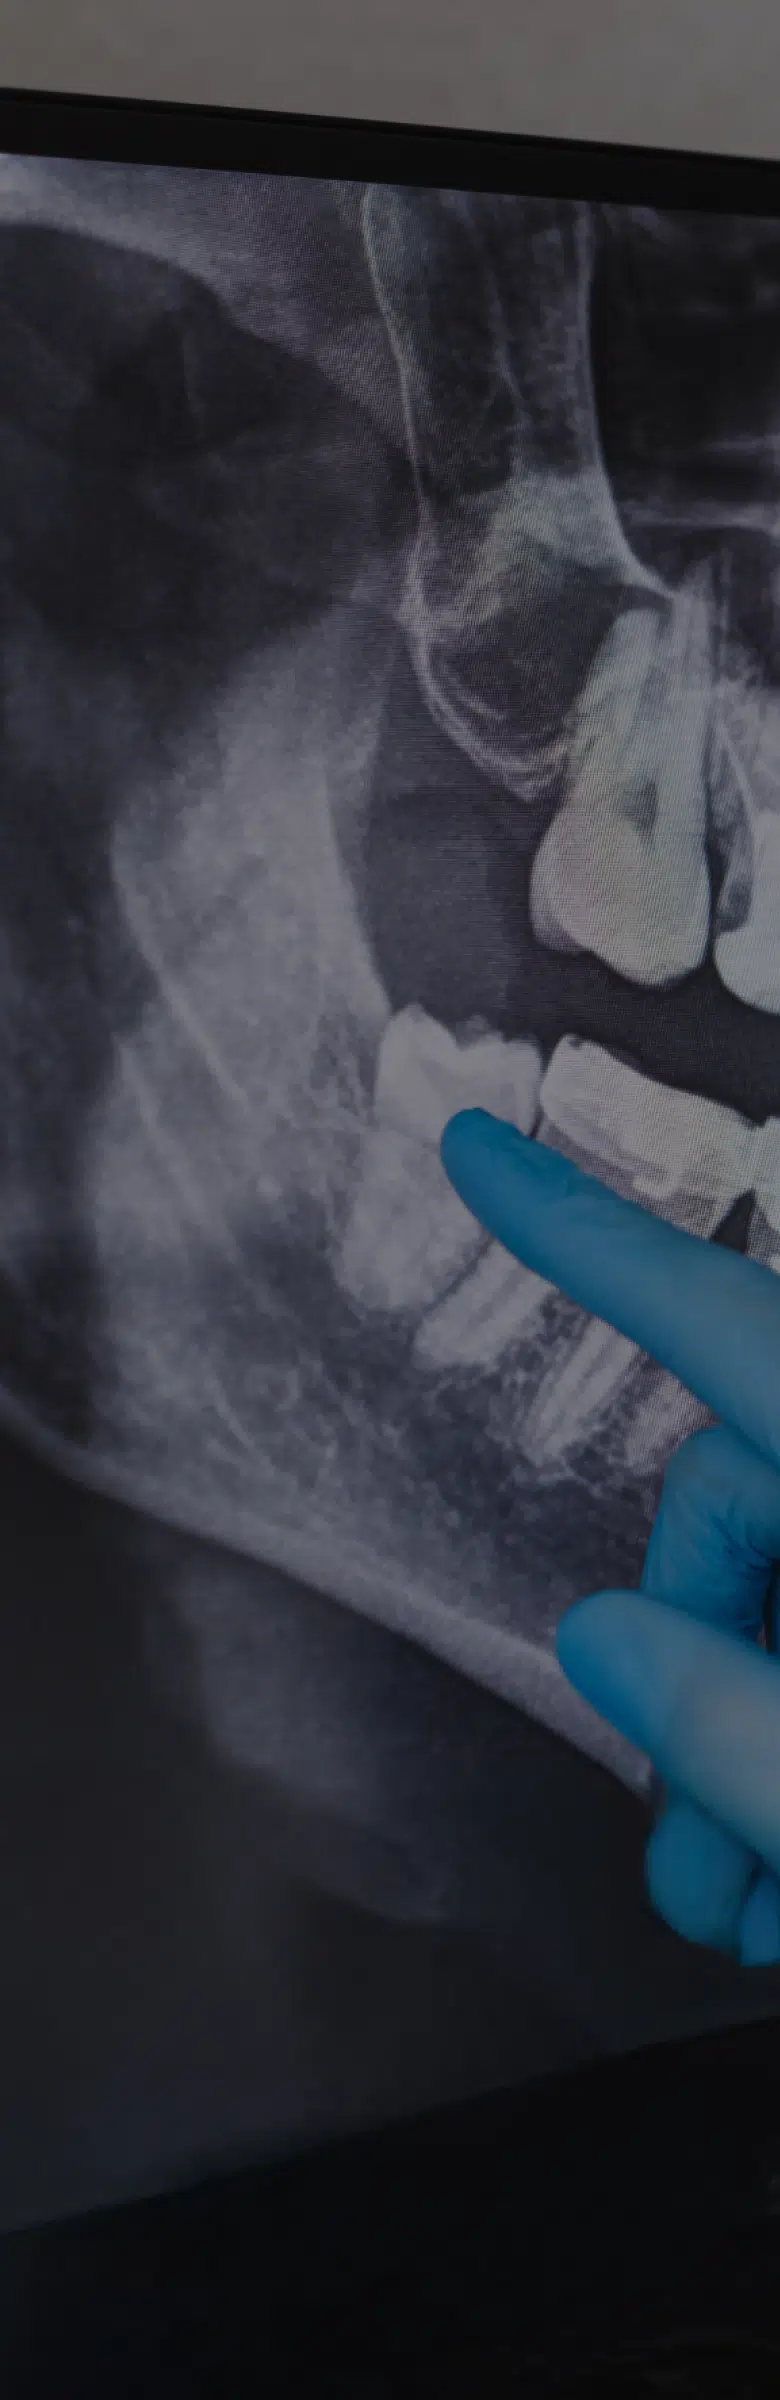

Cette intervention est souvent pratiquée de façon préventive, chez les patients jeunes ayant déjà suivi un traitement orthodontique. Un panoramique dentaire permettra de juger de la forme des germes et du manque de place. L’objectif étant d’éviter que l’éruption des ces dents de sagesse ne viennent dérégler l’alignement dentaire obtenu par le traitement orthodontique.

Avant l’extraction, votre chirurgien maxillo-facial effectuera en consultation une évaluation complète de votre santé bucco-dentaire, incluant des radiographies (panoramique dentaire) pour évaluer la position des dents de sagesse et détecter d’éventuelles complications. Vous déciderez alors avec votre chirurgien des modalités de l’anesthésie, locale ou générale.